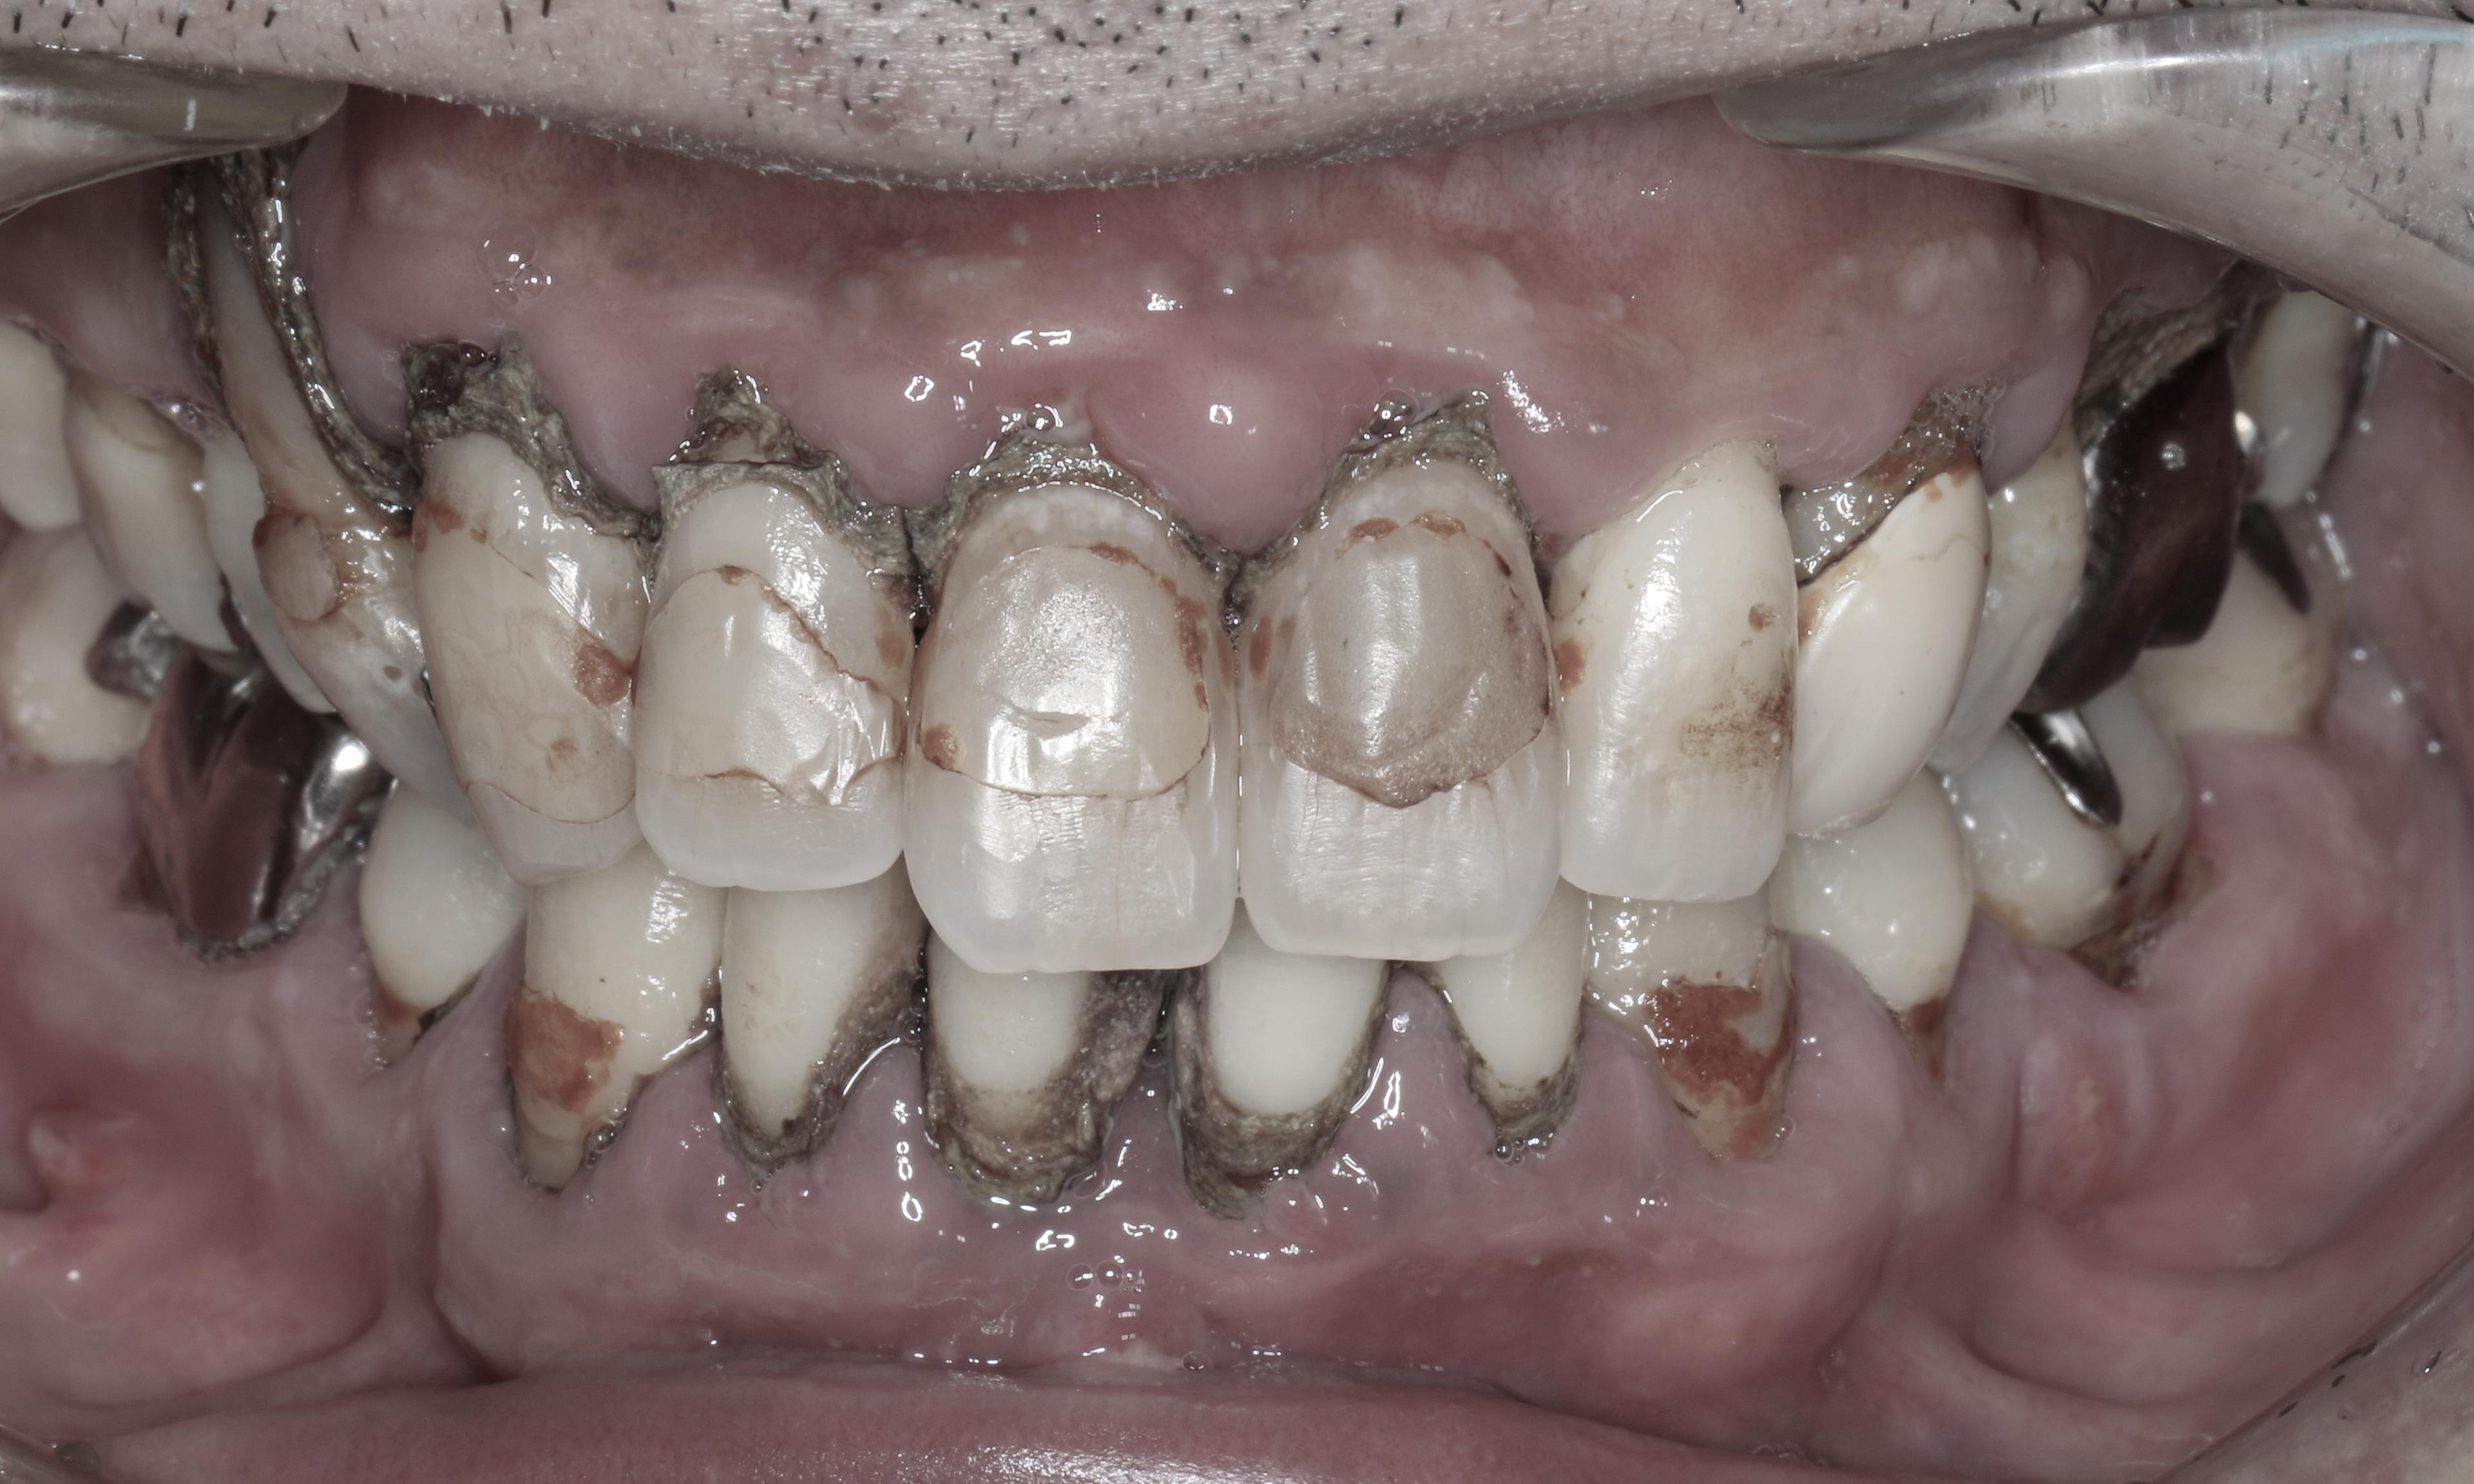

歯周ポケット測定不能。教科書的に100%抜歯の重度慢性歯周炎。原因除去療法とマイクロスコープを使った低侵襲の歯周組織再生療法により、抜歯を回避して回復した症例です。